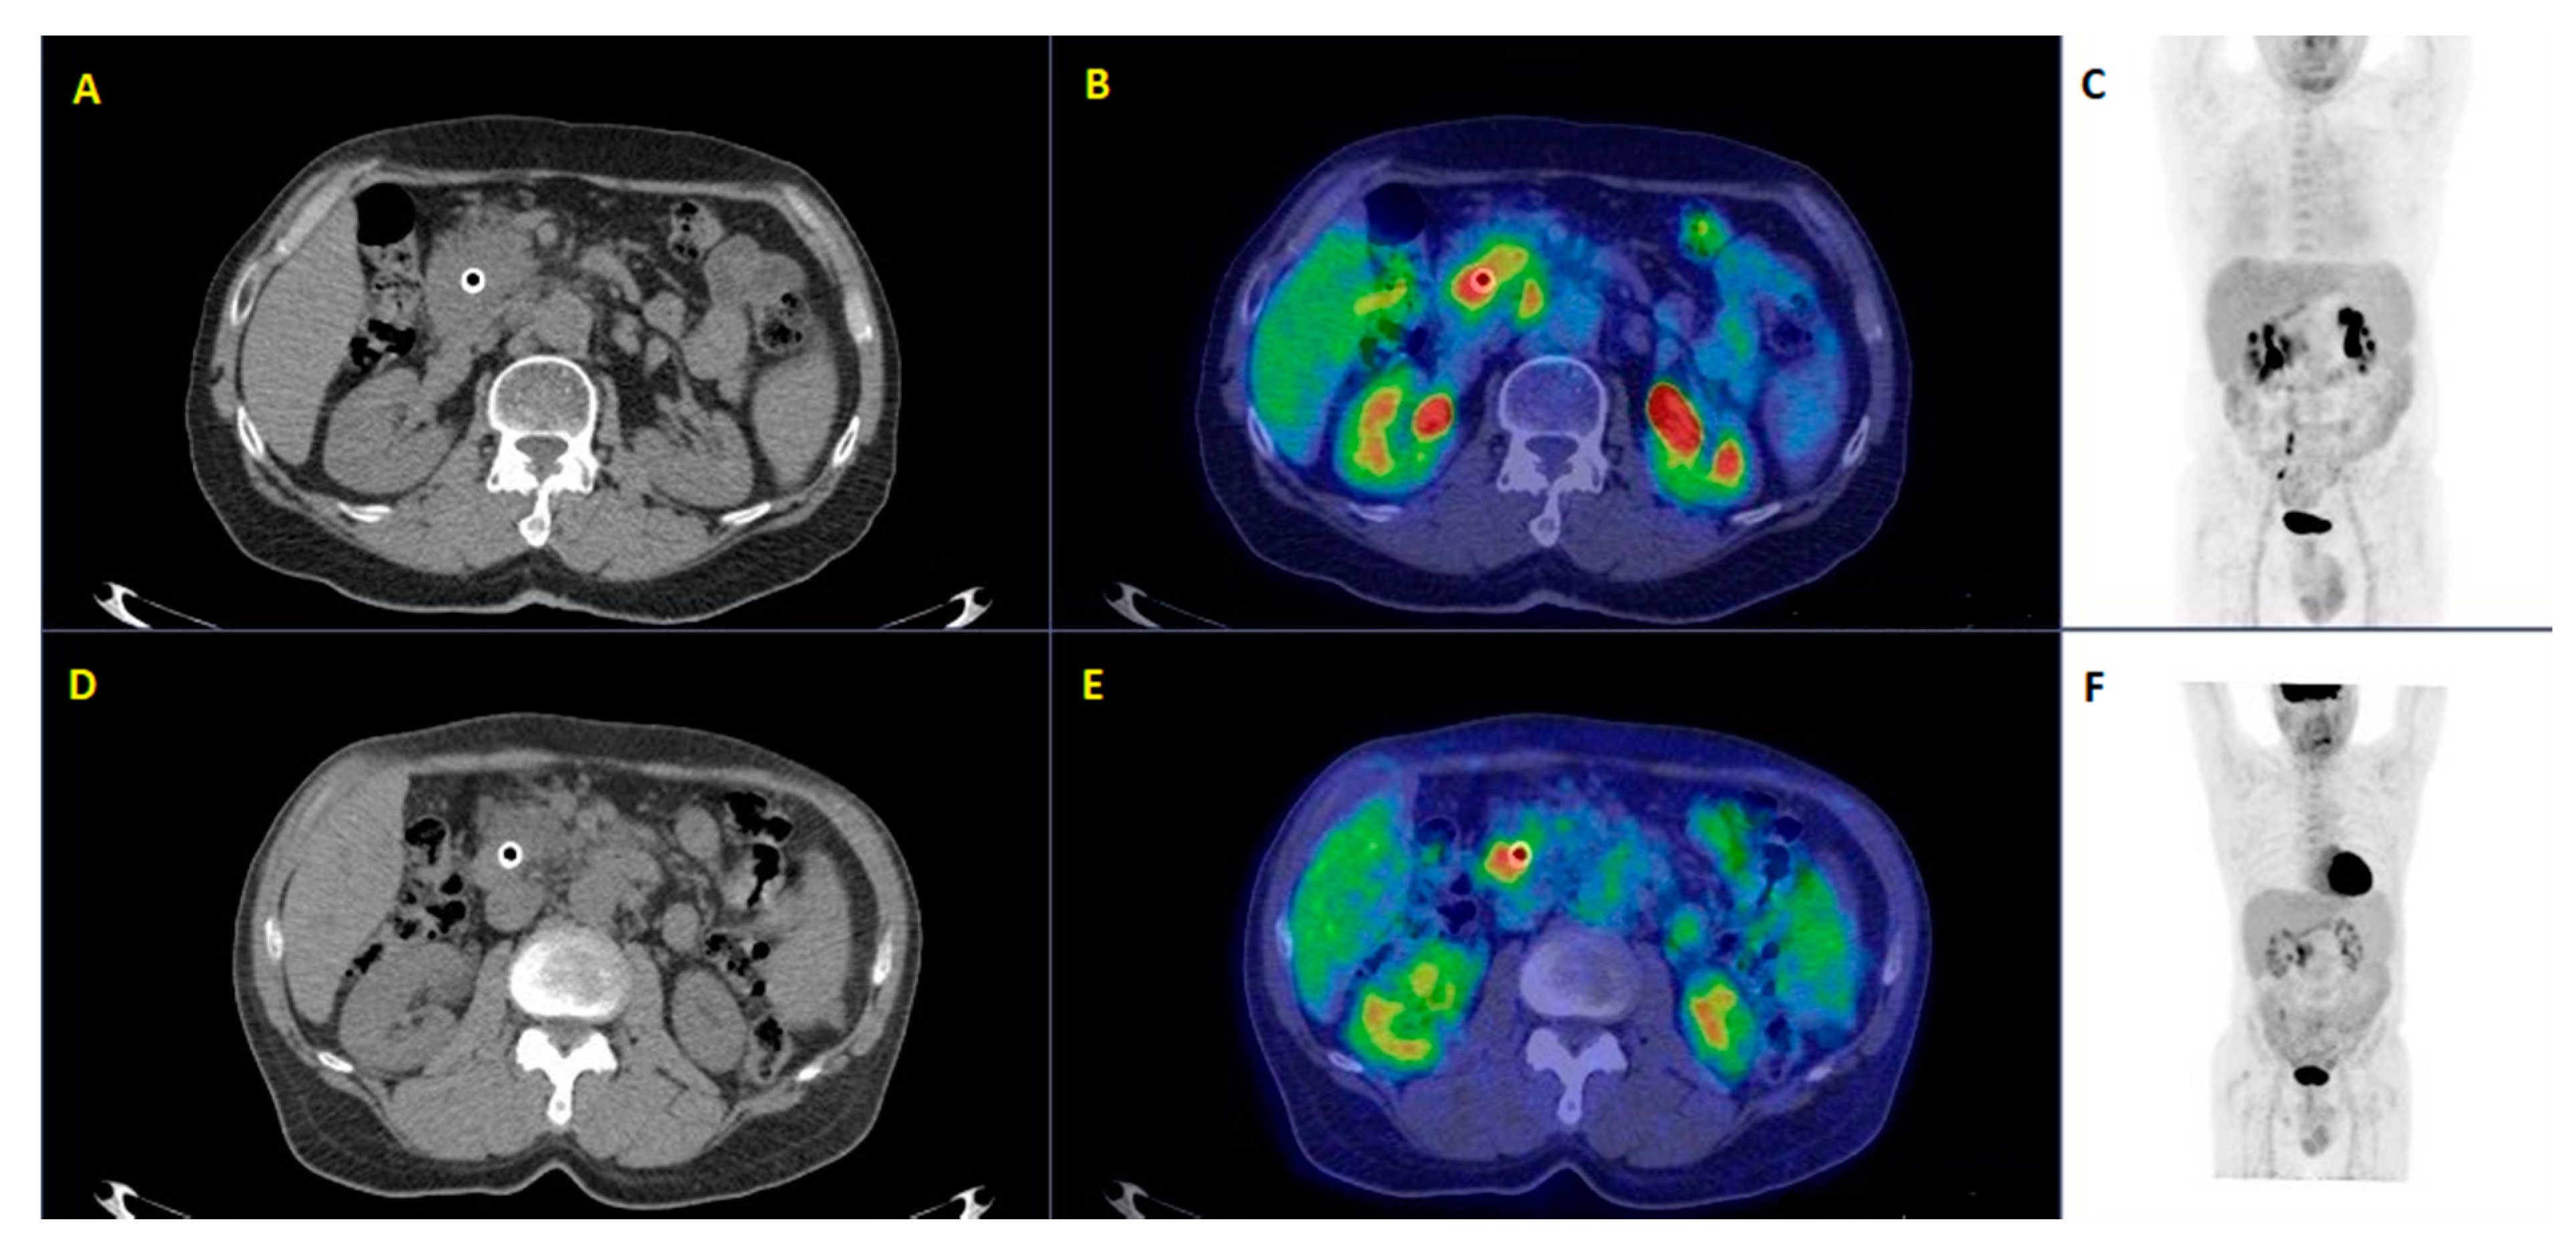

| 9 | Picchio et al. [24] | 2012 | Prospective study | 42 | Patients selection for helical tomotherapy with concurrent chemotherapy | PET/CT influenced the treatment strategy by detecting distant metastases not documented by CT, thus accurately selecting patients for hormonal-chemotherapy after induction chemotherapy |